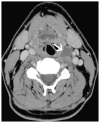

Cross-sectional imaging plays an important role in the evaluation of the retropharyngeal space (RPS) and the prevertebral space (PVS). Because of their deep location within the neck, lesions arising within these spaces are difficult, if not impossible, to evaluate on clinical examination. This article details the cross-sectional anatomy and imaging appearances of primary and secondary diseases involving the RPS and PVS, including metastasis and spread from adjacent spaces. The role of image-guided biopsy is also discussed.